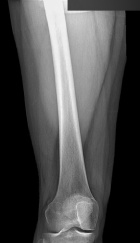

34 year old female with a three year history of right knee mass

Zoom image: Radiological image Radiological image.